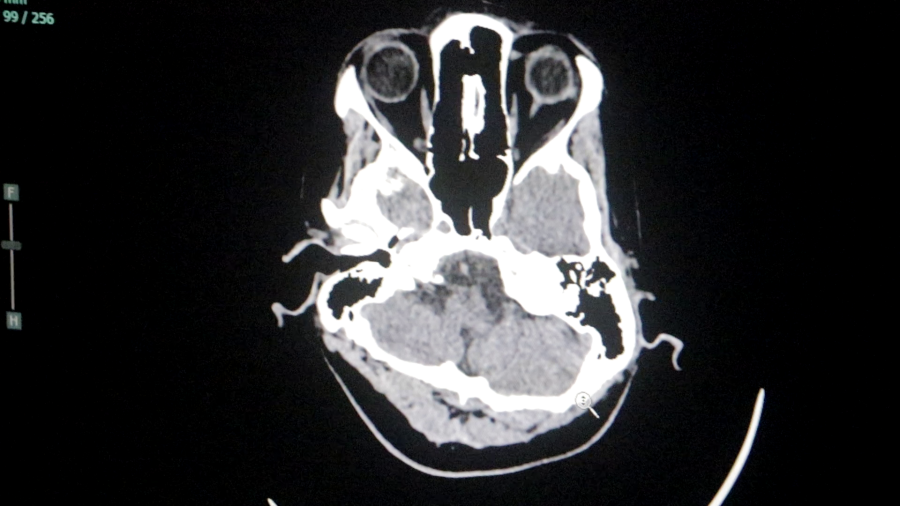

Durante el año, el servicio logró dar respuesta a un amplio abanico de patologías neurológicas de alta complejidad, incluyendo cuadros vasculares, tumorales y emergencias neuroquirúrgicas, consolidando al Parque de la Salud como centro de referencia regional.

En el área de emergentología, el servicio tuvo una fuerte intervención durante 2025, principalmente en casos de traumatismos de cráneo derivados de accidentes.

“Se pudo resolver la gran mayoría de los traumatismos de cráneo, siempre con el apoyo fundamental de los servicios de terapia intensiva y anestesia”, remarcó el Jefe del Servicio.